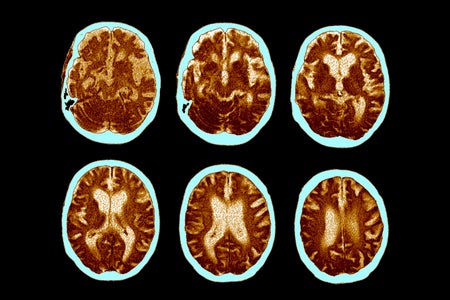

Alzheimer’s Drug Donanemab Helps Most When Taken Early in Disease

An Alzheimer’s drug that attacks the protein amyloid does not work as well in people with more advanced disease